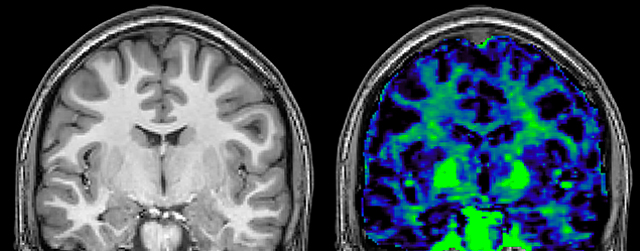

The techniques for measuring myelin have changed a lot over the years. “Since we are using the Elition, our myelin water images are much better. We're now acquiring 1 x 2 x 5 mm voxels and displaying at 1 x 1 x 2.5 mm. For a whole brain we can now measure the fraction of water in the myelin component in only about five or six minutes,” Dr. MacKay says.

of limiting MWI to the brain, even without the cerebellum, we can now spend about the same amount of time and scan the whole brain and the cervical spinal cord, which is a huge boost for us.” Dr. Rauscher says, “For MWI we perform 3D T2 with 32 or more echoes. This used to take a long time, but with Compressed SENSE we can decrease this to ten minutes for the whole head. Because of the large field of view (FOV) on the readout direction, we even get information from the brainstem, which we previously missed when we were using the GRASE approach. Having the whole head scan is nice because it has spatial resolution, orientation and FOV that are comparable to the standard 3D clinical MS scans, including the FLAIR and 3D T2, and a 3D T1 for brain volume.”

T1 - weighted

Myelin water imaging (echo 1)

With SENSE

With Compressed SENSE

Acquired resolution:

1 x 2 x 5 mm3

→

1.5 x 2 x 3 mm3

Number of echoes:

32 or 48

→

56

Echo spacing:

10 ms or 8 ms

→

7 ms

| | With SENSE | | With Compressed SENSE |

| Acquired resolution: | 1 x 2 x 5 mm3 | → | 1.5 x 2 x 3 mm3 |

| Number of echoes: | 32 or 48 | → | 56 |

| Echo spacing: | 10 ms or 8 ms | → | 7 ms |

T1 - Weighted, Myelin Water Fraction Superimposed

Spinal cord coverage

Smaller, more isotropic voxels

Excellent detail in quantitative maps

Images courtesy of Adam Dvorak, Department of Physics and Astronomy, University of British Columbia